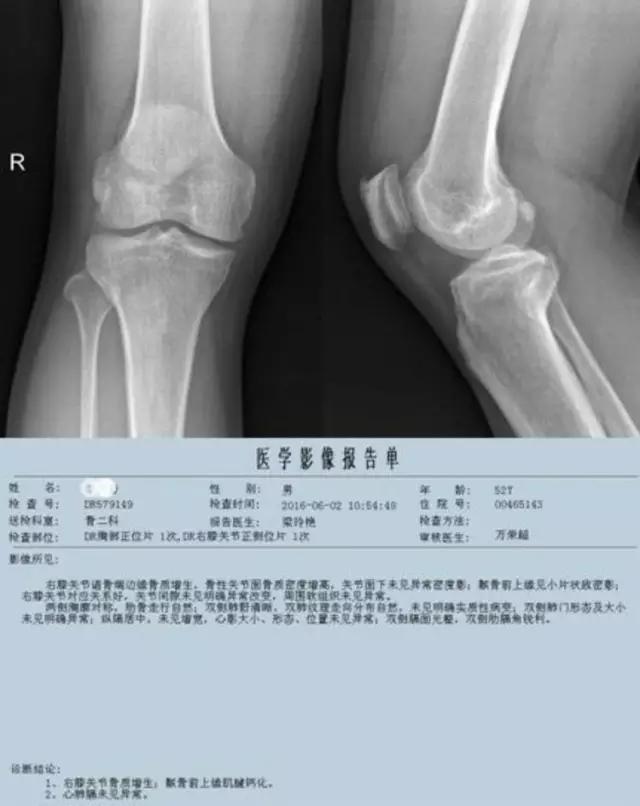

普通X线照片——

只能显示骨的改变,对早期膝关节炎等临床常见疾病的诊断意义不大,但"骨质增生"的诊断报告却常常影响病人一辈子!

下图是同一个病人的MRI照片,MRI显示的内容更多,包括骨与软组织等,很多早期的、细微的病变都能清晰显示,其诊断报告对病人造成的影响也更大!

膝关节OA是临床常见疾病,不断的磨损会引起一系列的改变,表现在X线照片上会出现以下的四大特征。

利用发病机理——